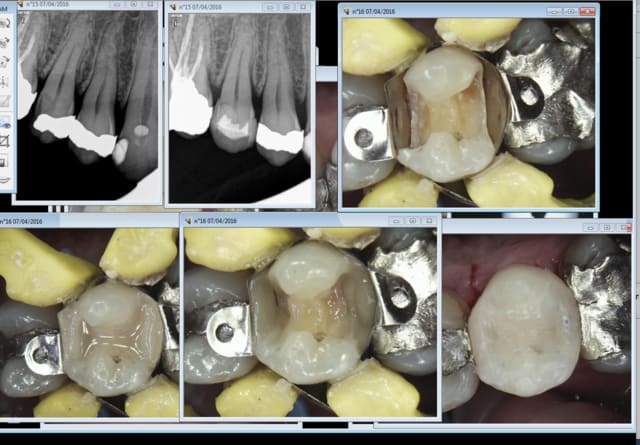

40,97 tarif sécu opposable pour un composite 3 faces. On essaie de meubler avec d'autres actes, radios détartrage pour ne pas foutre la clé sous la porte.

Et surtout on croise les doigts pour que les patients arrivent trop tard pour pouvoir faire ce type de restaurations. Heureusement c'est souvent le cas. -)

Ici 81,86 euros la séance, à peine de quoi payer les charges du cabinet. 2 mn pour le détartrage à 28,92 euros et 10 secondes pour les radios à 11,97 le tout 30 mn.

Pour bien gagner sa vie, d'après la rx initiale du premier post, faut faire une couronne sur la 6 et les compos sur 5 (et pourquoi pas 4) sont offerts au tarif conventionnel.

Le tarif conventionnel individuel de chacun des actes n'a aucun sens, mais le tarif global des 3 est acceptable.

Dans le cas présent, on peut, je pense, ne pas tomber dans ces travers: la 6 dévitalisée avec son gros amalgame mérite sa coiffe (risque de fracture, biocompatibilité des matériaux, risque de récidive carieuse sur 5 et 6 voire 7 si il y en a une, liée à l'étanchéité et à l'état de surface des reconstitutions qui ne permet pas d'éliminer la plaque de manière satisfaisante), et les amalgames sur 4 et 5 mérite aussi dans la mesure ou on refait le côté de manière moderne...et pour les mêmes raison que la 6

08/04/2016 à 13h17

Je ne vois pas pour quoi il ne va pas durer si la 6 pète. -))

Par contre j'attends depuis longtemps qu'elle pète la 6. -)

Au passage pas vu en septembre dernier la reprise en distal sur la 5. Ca n'est pas du sous traitement volontaire mais involontaire. -)

Ceci dit la carie étant profonde j'ai prévenu le patient d'éventuels problèmes de sensibilité, que j'attends également pour faire un bon IC coiffe tout bien remboursé. -)

Ici tu refais tout le cadran : onlay 17, Ceram 16, onlay 15 et onlay 14.

Tu as une idée de ce qu'il va lui rester à charge à ce patient qui n'a pas mal et ne consulte que pour un amalgame cassé ? -)))

Chiotte d'ailleurs je pensais que c'était la 16 d'ailleurs qui avait fini par péter ! -)))

Au passage le problème de sur-sous tt se repose de la meme facon entre onlay - composite foulé et Onlay-couronne. Question qui ne se poserait pas si ces actes étaient pris en charge de facon cohérente.